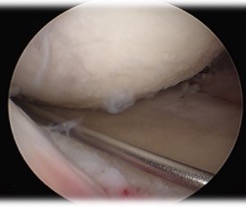

Bone in slot techique

- maintain meniscal attachment

- prepare bone graft to fit in 8 mm slot

Small medial or lateral parapatella to make trough

- prepare meniscus

- leave margin of meniscus to allow suture to